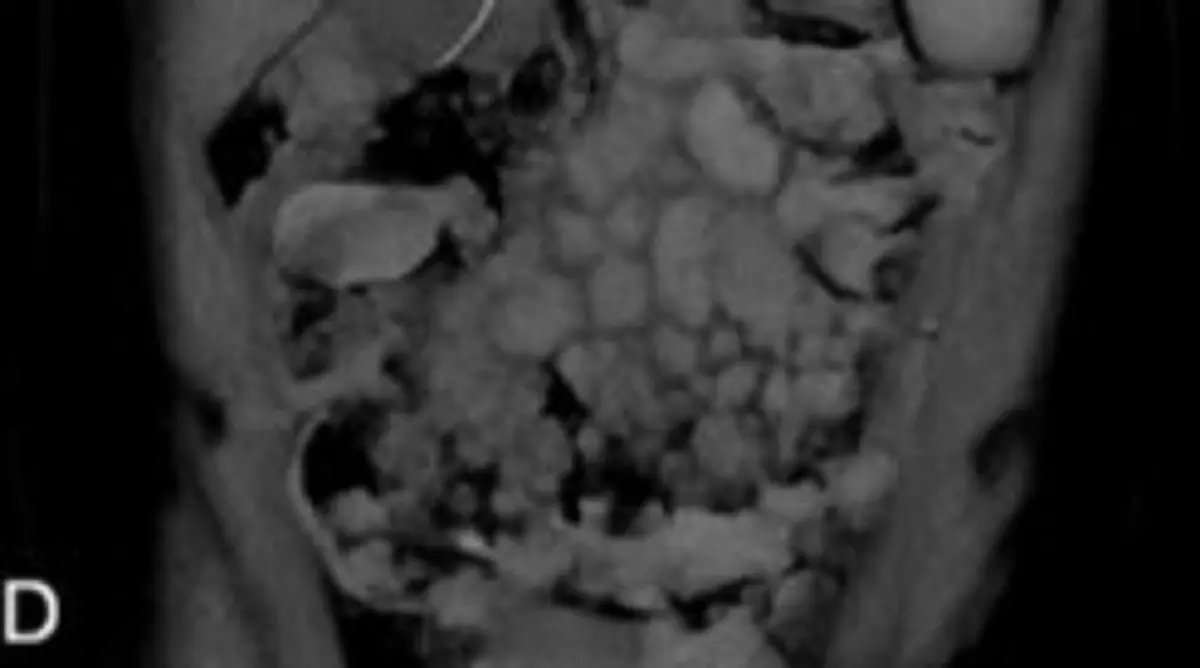

멕시코 호세 엘레우테리오 곤살레스대병원 내과 의료진에 따르면, 23세 여성이 복통·빈혈 등과 같은 전신 증상이 나타나 입원 후 검사를 받았다. 그 결과, 여성은 버킷림프종을 진단받았다.

버킷림프종은 백혈구 중 B림프구에서 기인하는 혈액암으로, 림프계에 발생한다. 버킷림프종은 비호지킨 림프종에 속해서 빠르게 진행되는 공격형 림프종이다. 림프종은 백혈구 중 하나인 림프구가 악성 세포로 변한 종양이다. 골수나 혈관, 복부 기관 등으로 침범할 때가 많아 침범 부위에 따라 두통, 구토, 복부 비대가 나타난다.

여성에게는 원인을 알 수 없는 황달, 췌장염, 폐 질환 등의 증상도 함께 나타났다. 이후 치료 과정에서 15cm 길이의 회충이 배출됐고, 대변 검사로 회충 감염을 뒤늦게 확인했다. 항기생충 치료에도 불구하고 여성은 난치성 패혈증 쇼크로 결국 사망했다.

의료진은 “환자는 버킷림프종으로 인해 심각한 면역저하 상태였다”며 “이 상황에서 회충이 감염되면서 췌장, 폐 등 여러 장기로 퍼지며 합병증을 유발한 것”이라고 말했다. 실제로 면역저하 환자에서는 기생충 감염이 전형적 징후 없이 숨어 있다가 다른 중증 질환에 가려져 늦게 발견될 수 있다. 의료진은 “면역저하 환자가 중증 질환에 가려진 감염을 놓치면 생존 기회를 잃을 수 있음을 시사한다”고 전했다.